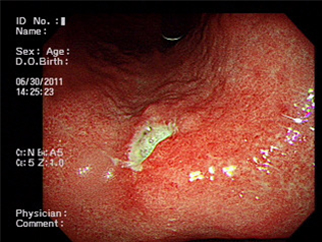

상부내시경으로는 위 용종, 조기위암 하부내시경으로는 대장의 용종(폴립) 및 조기 대장암, 소화관 이물의 제거, 식도 및 위정맥류, 소화관 출혈 및 천공, 경피 내시경적 위루술 (내시경으로 위 내부를 보면서 복벽을 통해 위로 튜브를 삽입하는 시술) 등 내시경을 통한 치료 및 치료적 시술을 시행하고 있습니다.

3) 내시경적 용종절제술 및 점막(하) 절제술

양성 종양은 과거에는 관찰 또는 수술적 절제를 하였으나 최근에는 너무 크지 않은 경우 내시경적으로 출혈 없이 간단히 제거할 수 있으며 이것은 치료적인 측면 뿐만 아니라 종양 전체 조직을 검사할 수 있어 정확한 진단에도 매우 도움이 됩니다.

더욱이 악성 종양(암)에 대해서도 최근에는 임파절 전이가 없는 조기암인 경우 적절한 경우에 내시경적 절제술이 치료로 이용되고 있습니다.